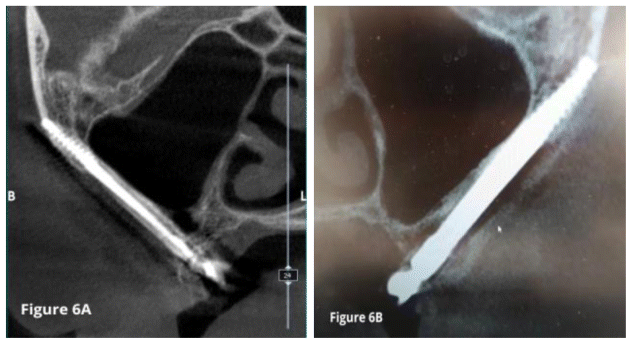

A follow-up CBCT scan was performed two years after surgery. The Schneiderian membrane showed physiological ventilation with no signs of inflammation (Figure 6).